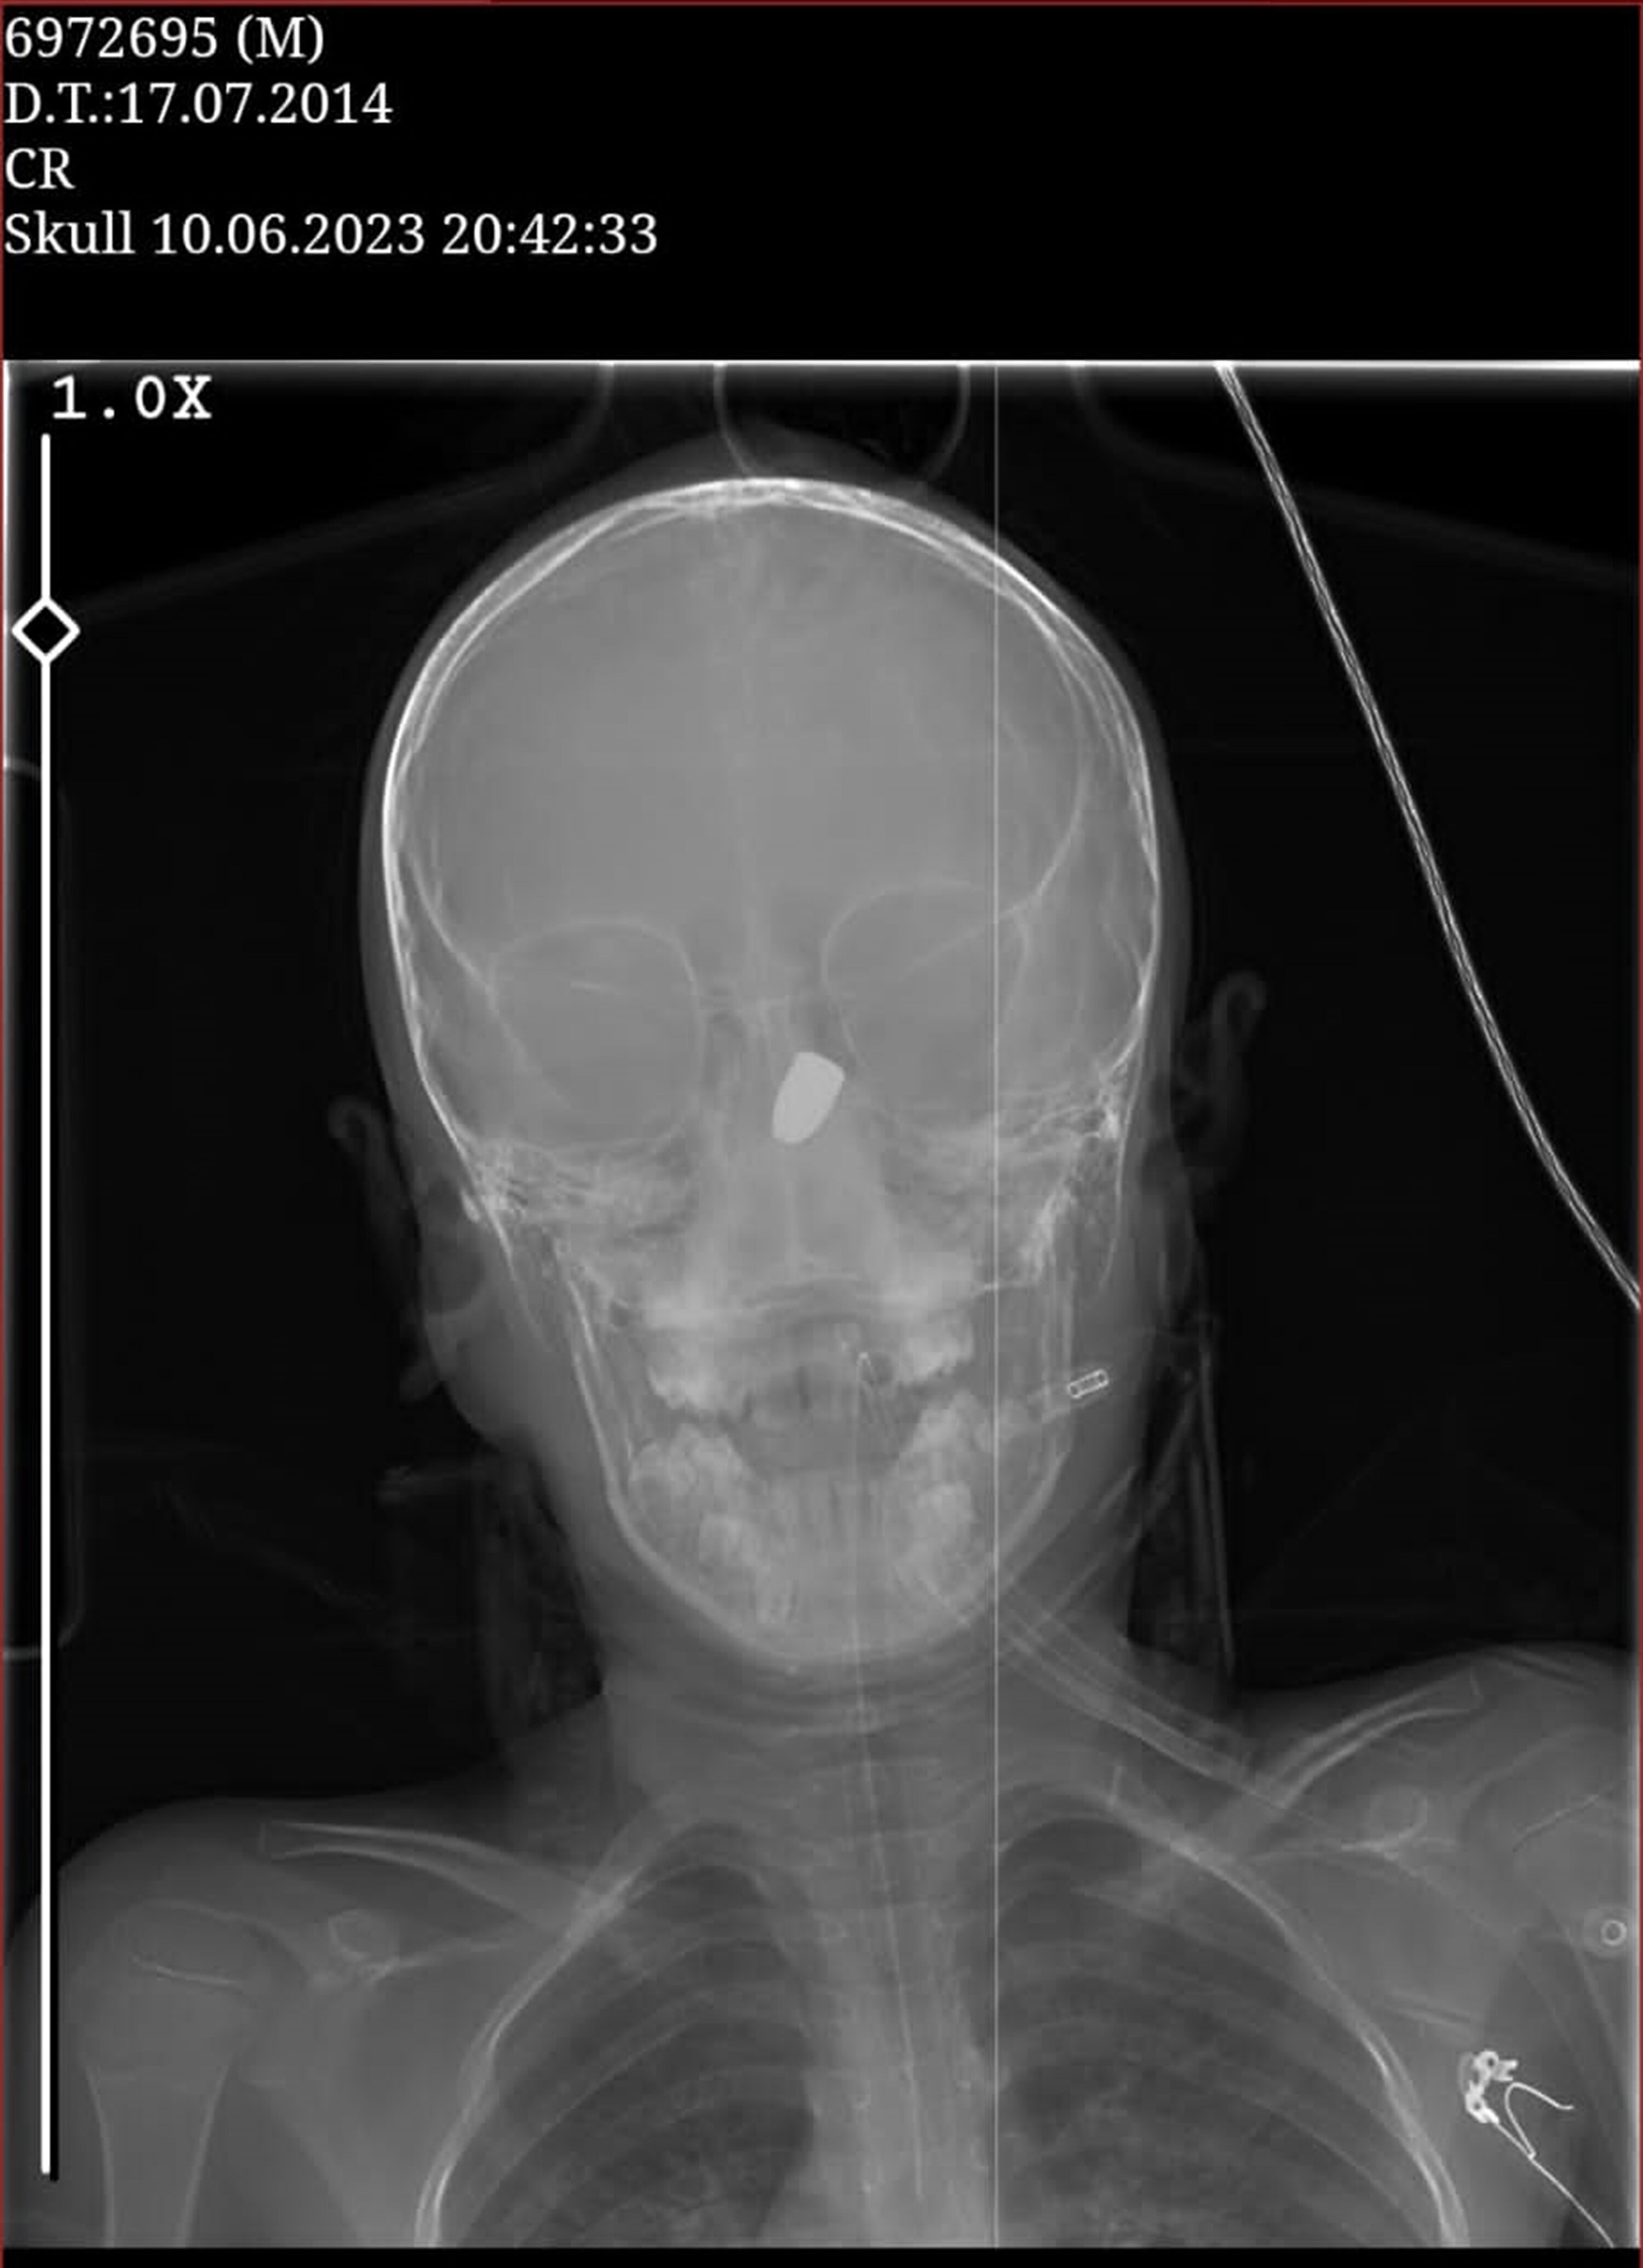

Olay, 10 Haziran'da Çukurçayır Mahallesi'nde meydana geldi. Site parkında arkadaşları ile oynayan Kerem Can Özdemir, birden kanlar içerisinde yere yığıldı. Çağrılan sağlık ekiplerince KTÜ Farabi Hastanesi'ne kaldırılan Özdemir'in çekilen tomografisinde başına yorgun mermi isabet ettiği tespit edildi. Olay ile ilgili başlatılan soruşturma sürerken, küçük çocuğun yere yığıldığı anlar da sitenin güvenlik kamerasına yansıdı. Silahı ateşleyenin belirlenmesi için İl Emniyet Müdürlüğü bünyesinde özel ekip oluşturuldu. Bölgede birçok güvenlik kamerasını mercek altına alan ekipler, şüphelinin izini sürüyor.

MERMİ 6 SANTİMETRE DERİNDE

Yoğun bakım servisinde tedavisi süren Kerem Can Özdemir’in, risk oluşturduğu için ameliyata alınmadığı belirtildi. Beyninin 6 santimetre derinine saplanan mermi çekirdeğiyle yaşam savaşı veren Kerem Can’ın 37 haftalık hamile annesi Fatma Özdemir, olaydan 2 gün sonra aynı hastanede erken doğum yaptı. Prematüre doğup, kuvözde tutulan bebeklerini kucaklarına almayı bekleyen aile, aynı hastanenin koridorunda bir yandan da yaralı çocuklarından gelecek iyi haberi bekliyor. Özdemir ailesi hem sevinci hem de hüznü bir arada yaşıyor.